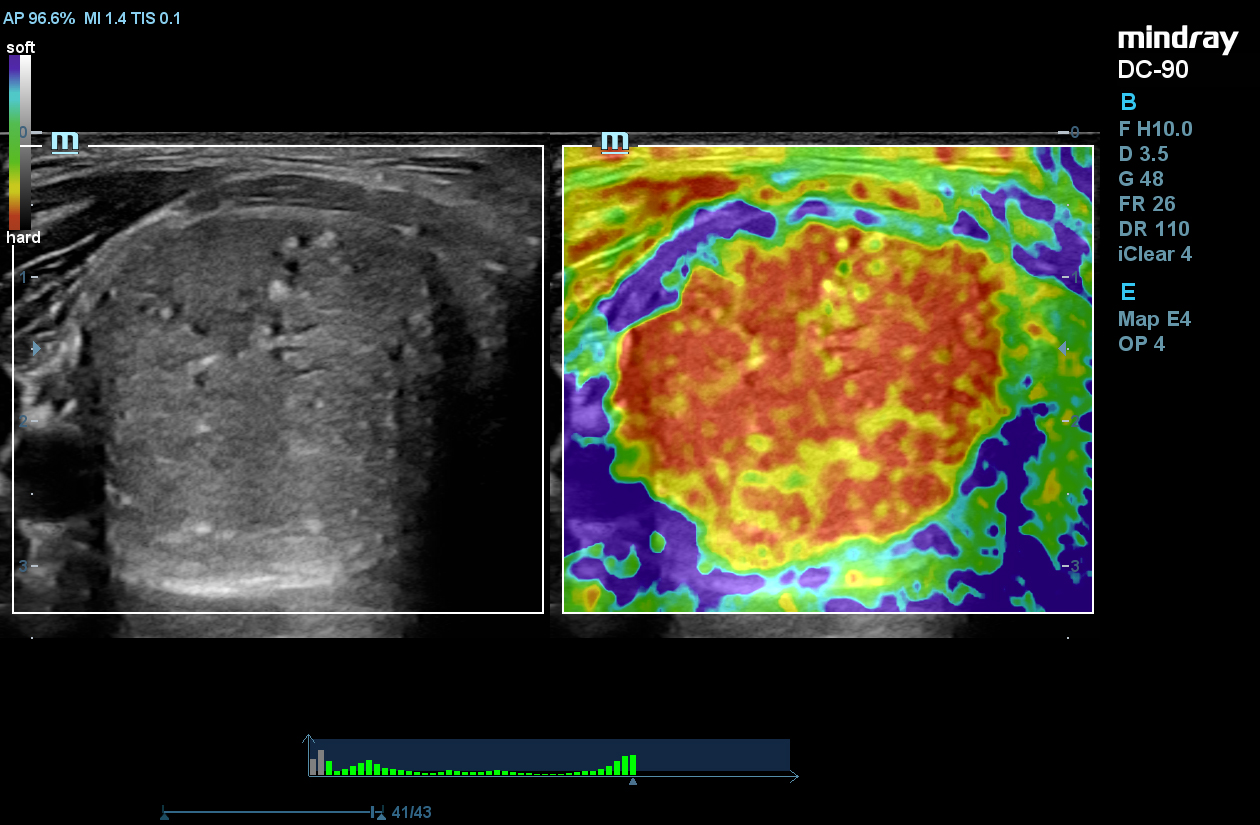

STE

Mindray’s Sound Touch Elastography (STE) utilizes exclusive Ultra-Wide Beam Tracking technology to provide comprehensive quantification metrics and dynamic visual display of tissue stiffness for enhanced diagnostic confidence. Using real-time and rapid data acquisition from a wide beam single pulse, STE is designed to reduce noise caused by motion artifact for improved efficiency and accuracy of measurements.